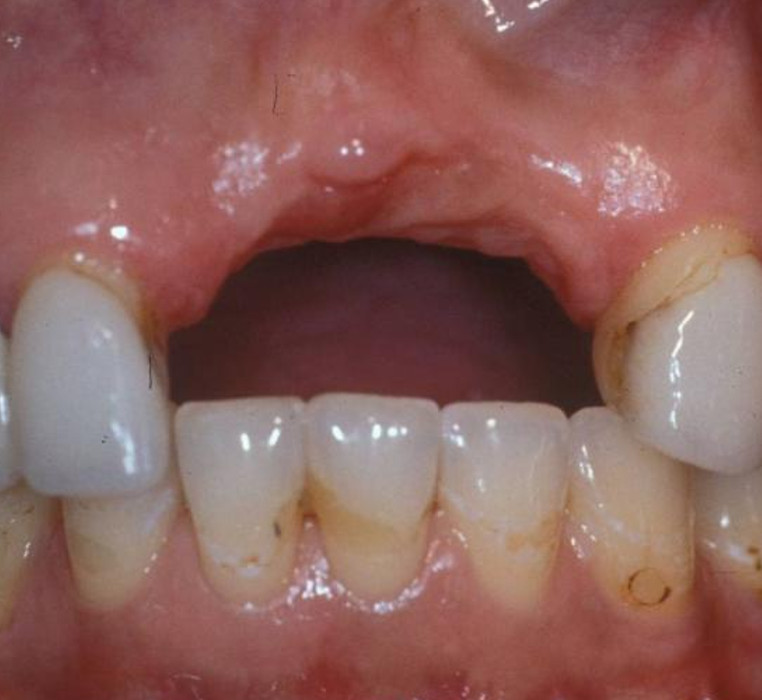

Cosmetic Crown Lengthening

Before

After